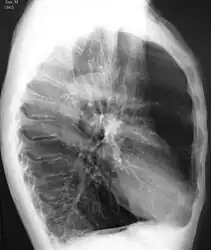

A chest X-ray and complete blood count may be useful to exclude other conditions at the time of diagnosis.[82] Characteristic signs on X-ray are hyperinflated lungs, a flattened diaphragm, increased retrosternal airspace, and bullae, while it can help exclude other lung diseases, such as pneumonia, pulmonary edema, or a pneumothorax.[83] A high-resolution CT scan of the chest may show the distribution of emphysema throughout the lungs and can also be useful to exclude other lung diseases.[25] Unless surgery is planned, however, this rarely affects management.[25] A saber-sheath trachea deformity may also be present.[84] An analysis of arterial blood is used to determine the need for oxygen; this is recommended in those with an FEV1 less than 35% predicted, those with a peripheral oxygen saturation less than 92%, and those with symptoms of congestive heart failure.[24] In areas of the world where alpha-1 antitrypsin deficiency is common, people with COPD (particularly those below the age of 45 and with emphysema affecting the lower parts of the lungs) should be considered for testing.[24]